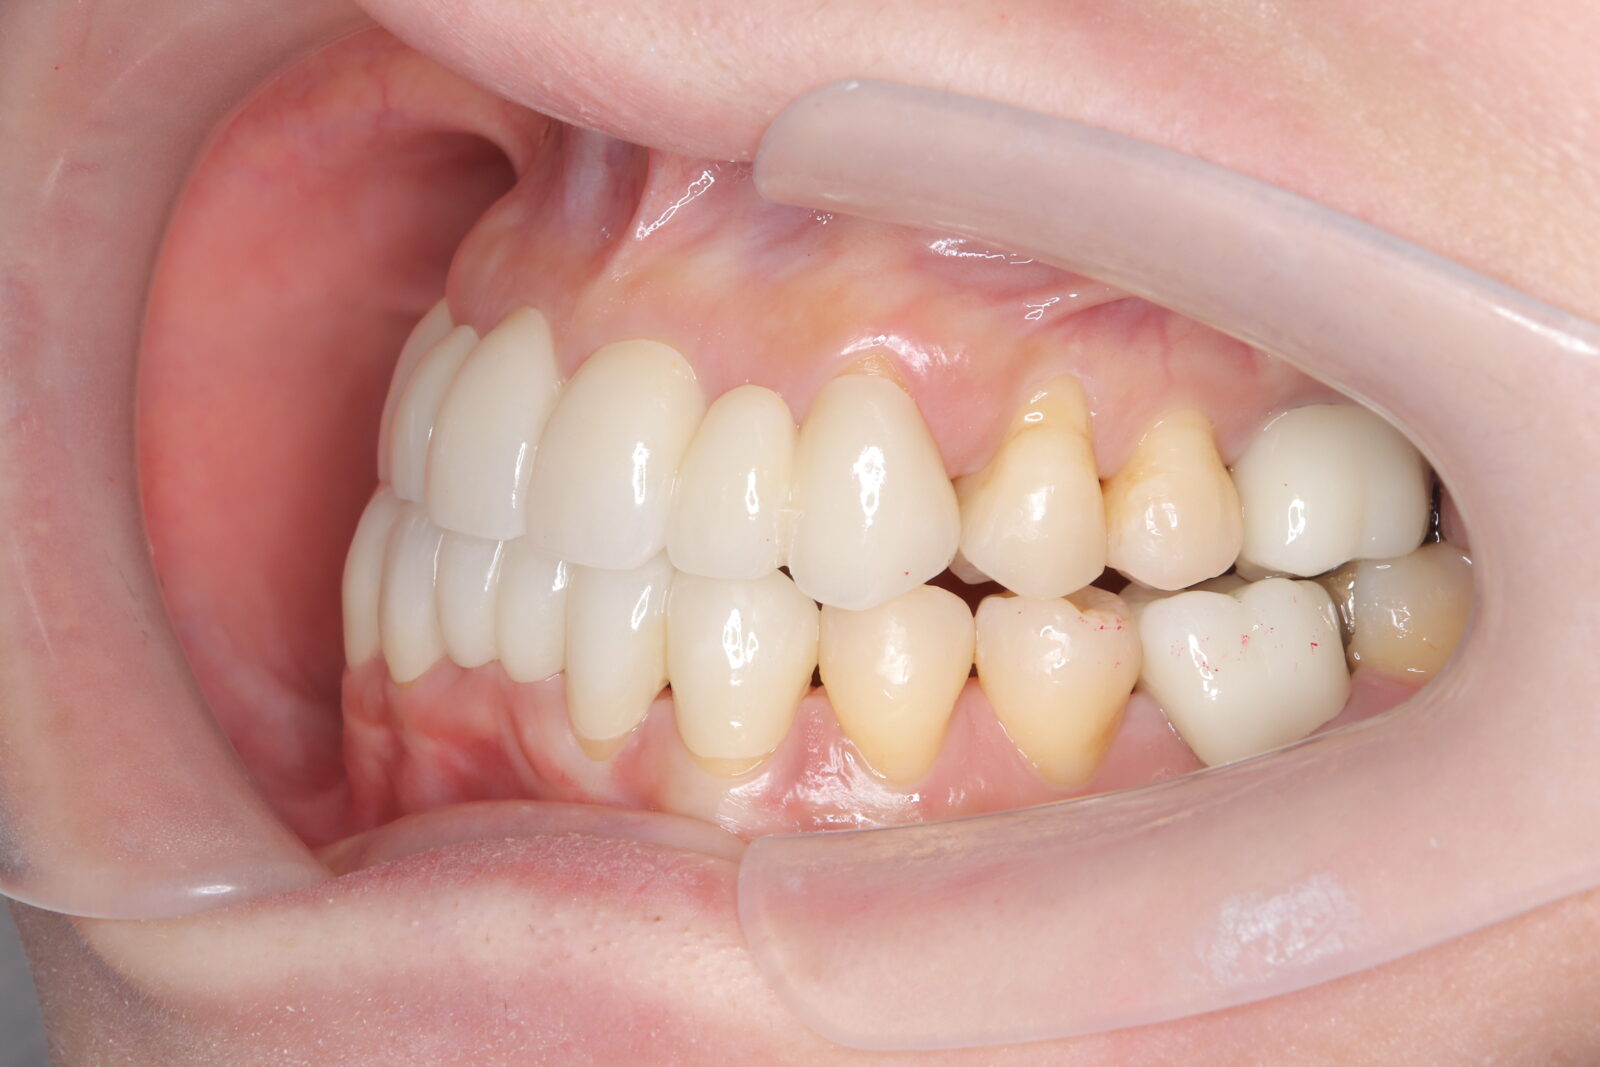

職業柄抜歯をすることができない患者様の症例

職業柄抜歯をすることができないため、小臼歯も親知らずも非抜歯の矯正となりました。 それでは歯を並べるためのスペースを確保できない。歯根の形状を分析し、可能な限り歯冠修復で前歯のサイズを小さくして、歯を動かすためのスペースを作り矯正をスタートした。 下顎前歯歯並びきれないこと、理想的な噛み合わせの獲得は難しいことをご理解いただき治療スタートした。 終了時に初期時の不自由がないことを確認済み。